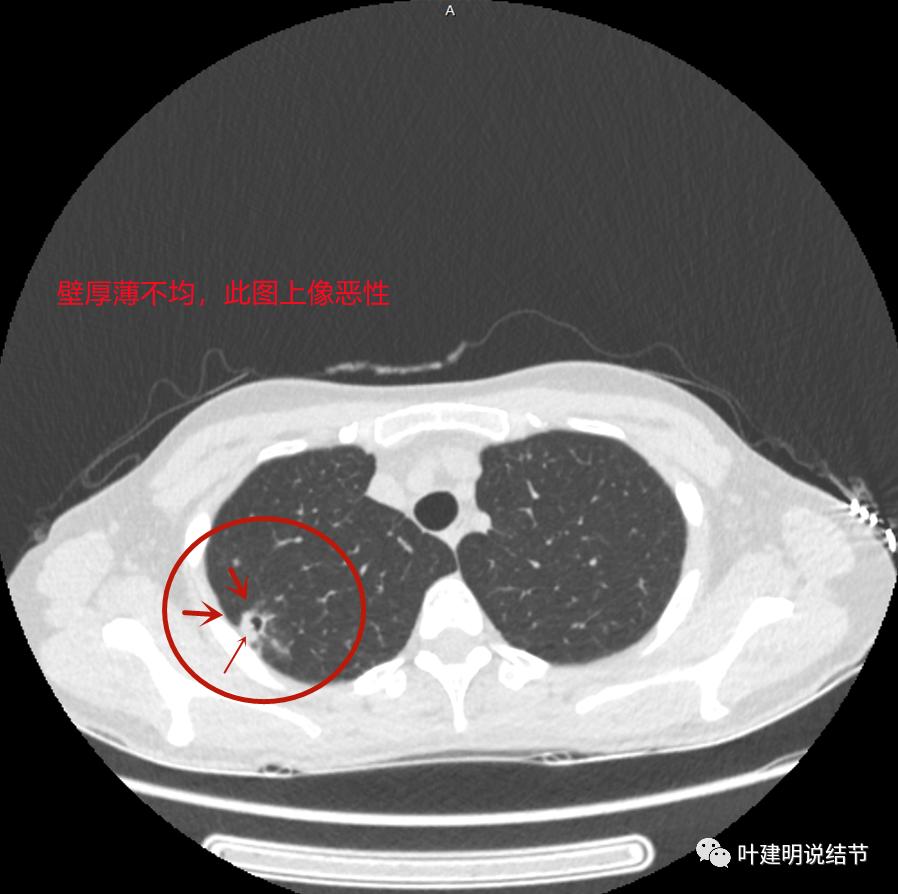

上图与恶性较为符合,空洞性病灶,壁厚薄不均,增厚部分还凹凸不平(细红色箭头所指)

上图磨玻璃部分密度过低,且与正常肺组织界限模糊(砖色箭头),粉色箭头示囊壁密度过高的点状,蓝色箭头示邻近胸膜处的增厚

上图也像恶性,但整个囊壁的密度感觉过高了点,边缘磨玻璃淡、散且模糊,邻近胸膜有增厚

上图病灶的边相对比较光,没有毛刺征,邻近胸膜增厚

上图病灶边缘比较平直,没有膨胀性(桔色箭头),旁边的磨玻璃影淡且界限不清,邻近胸膜增厚。